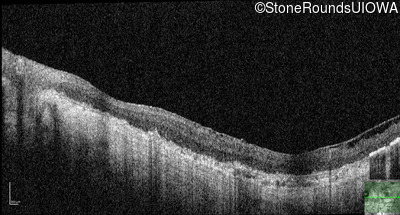

Age at visit: 33 years

OD OS